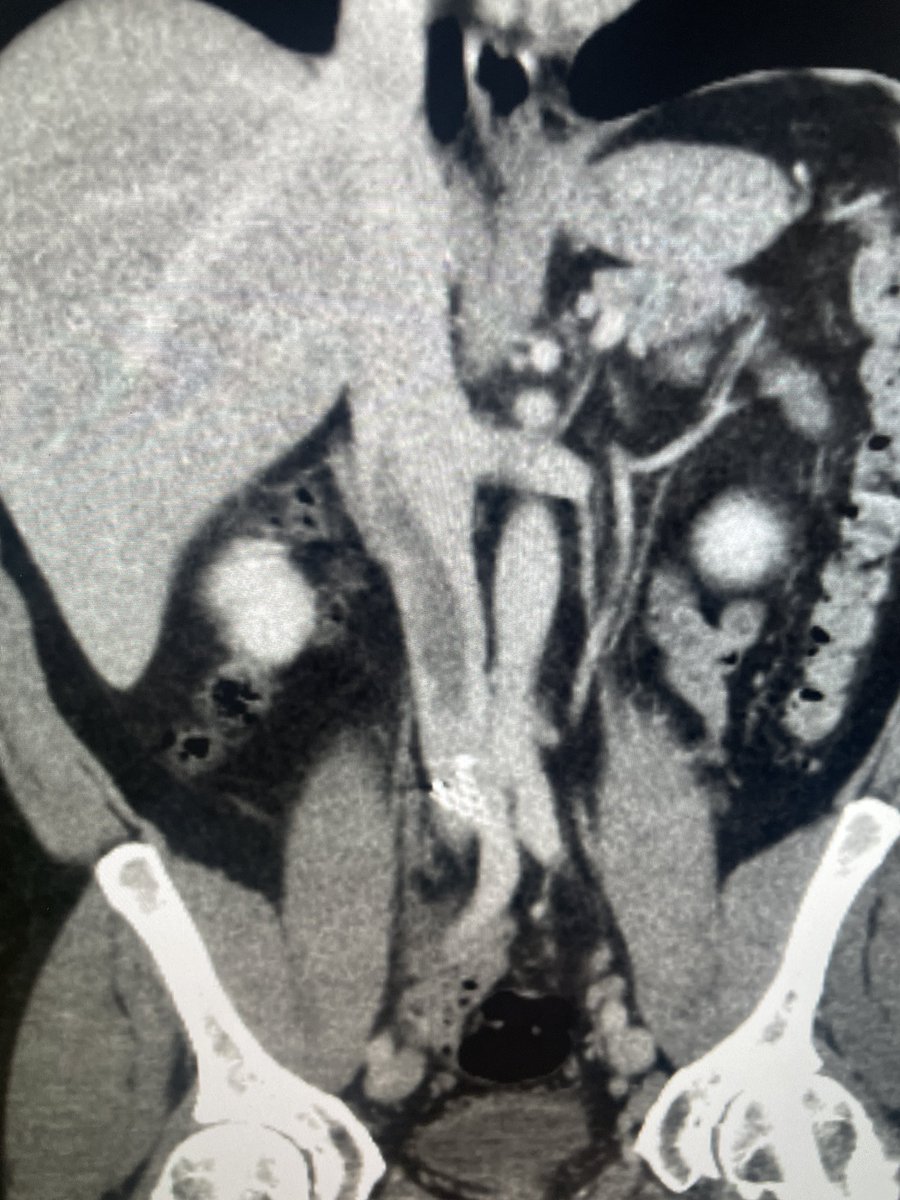

Genicular Artery Embolization for knee osteoarthritis. No skin mottling or ulcers. @IrColorado